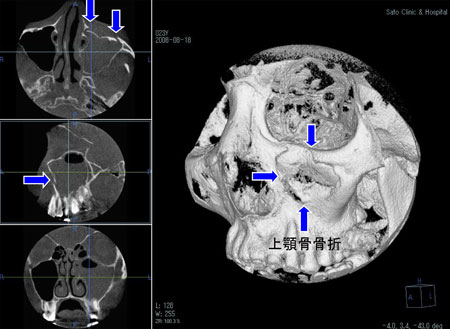

2.上顎骨骨折

上あごの骨の骨折です。

上顎骨骨折